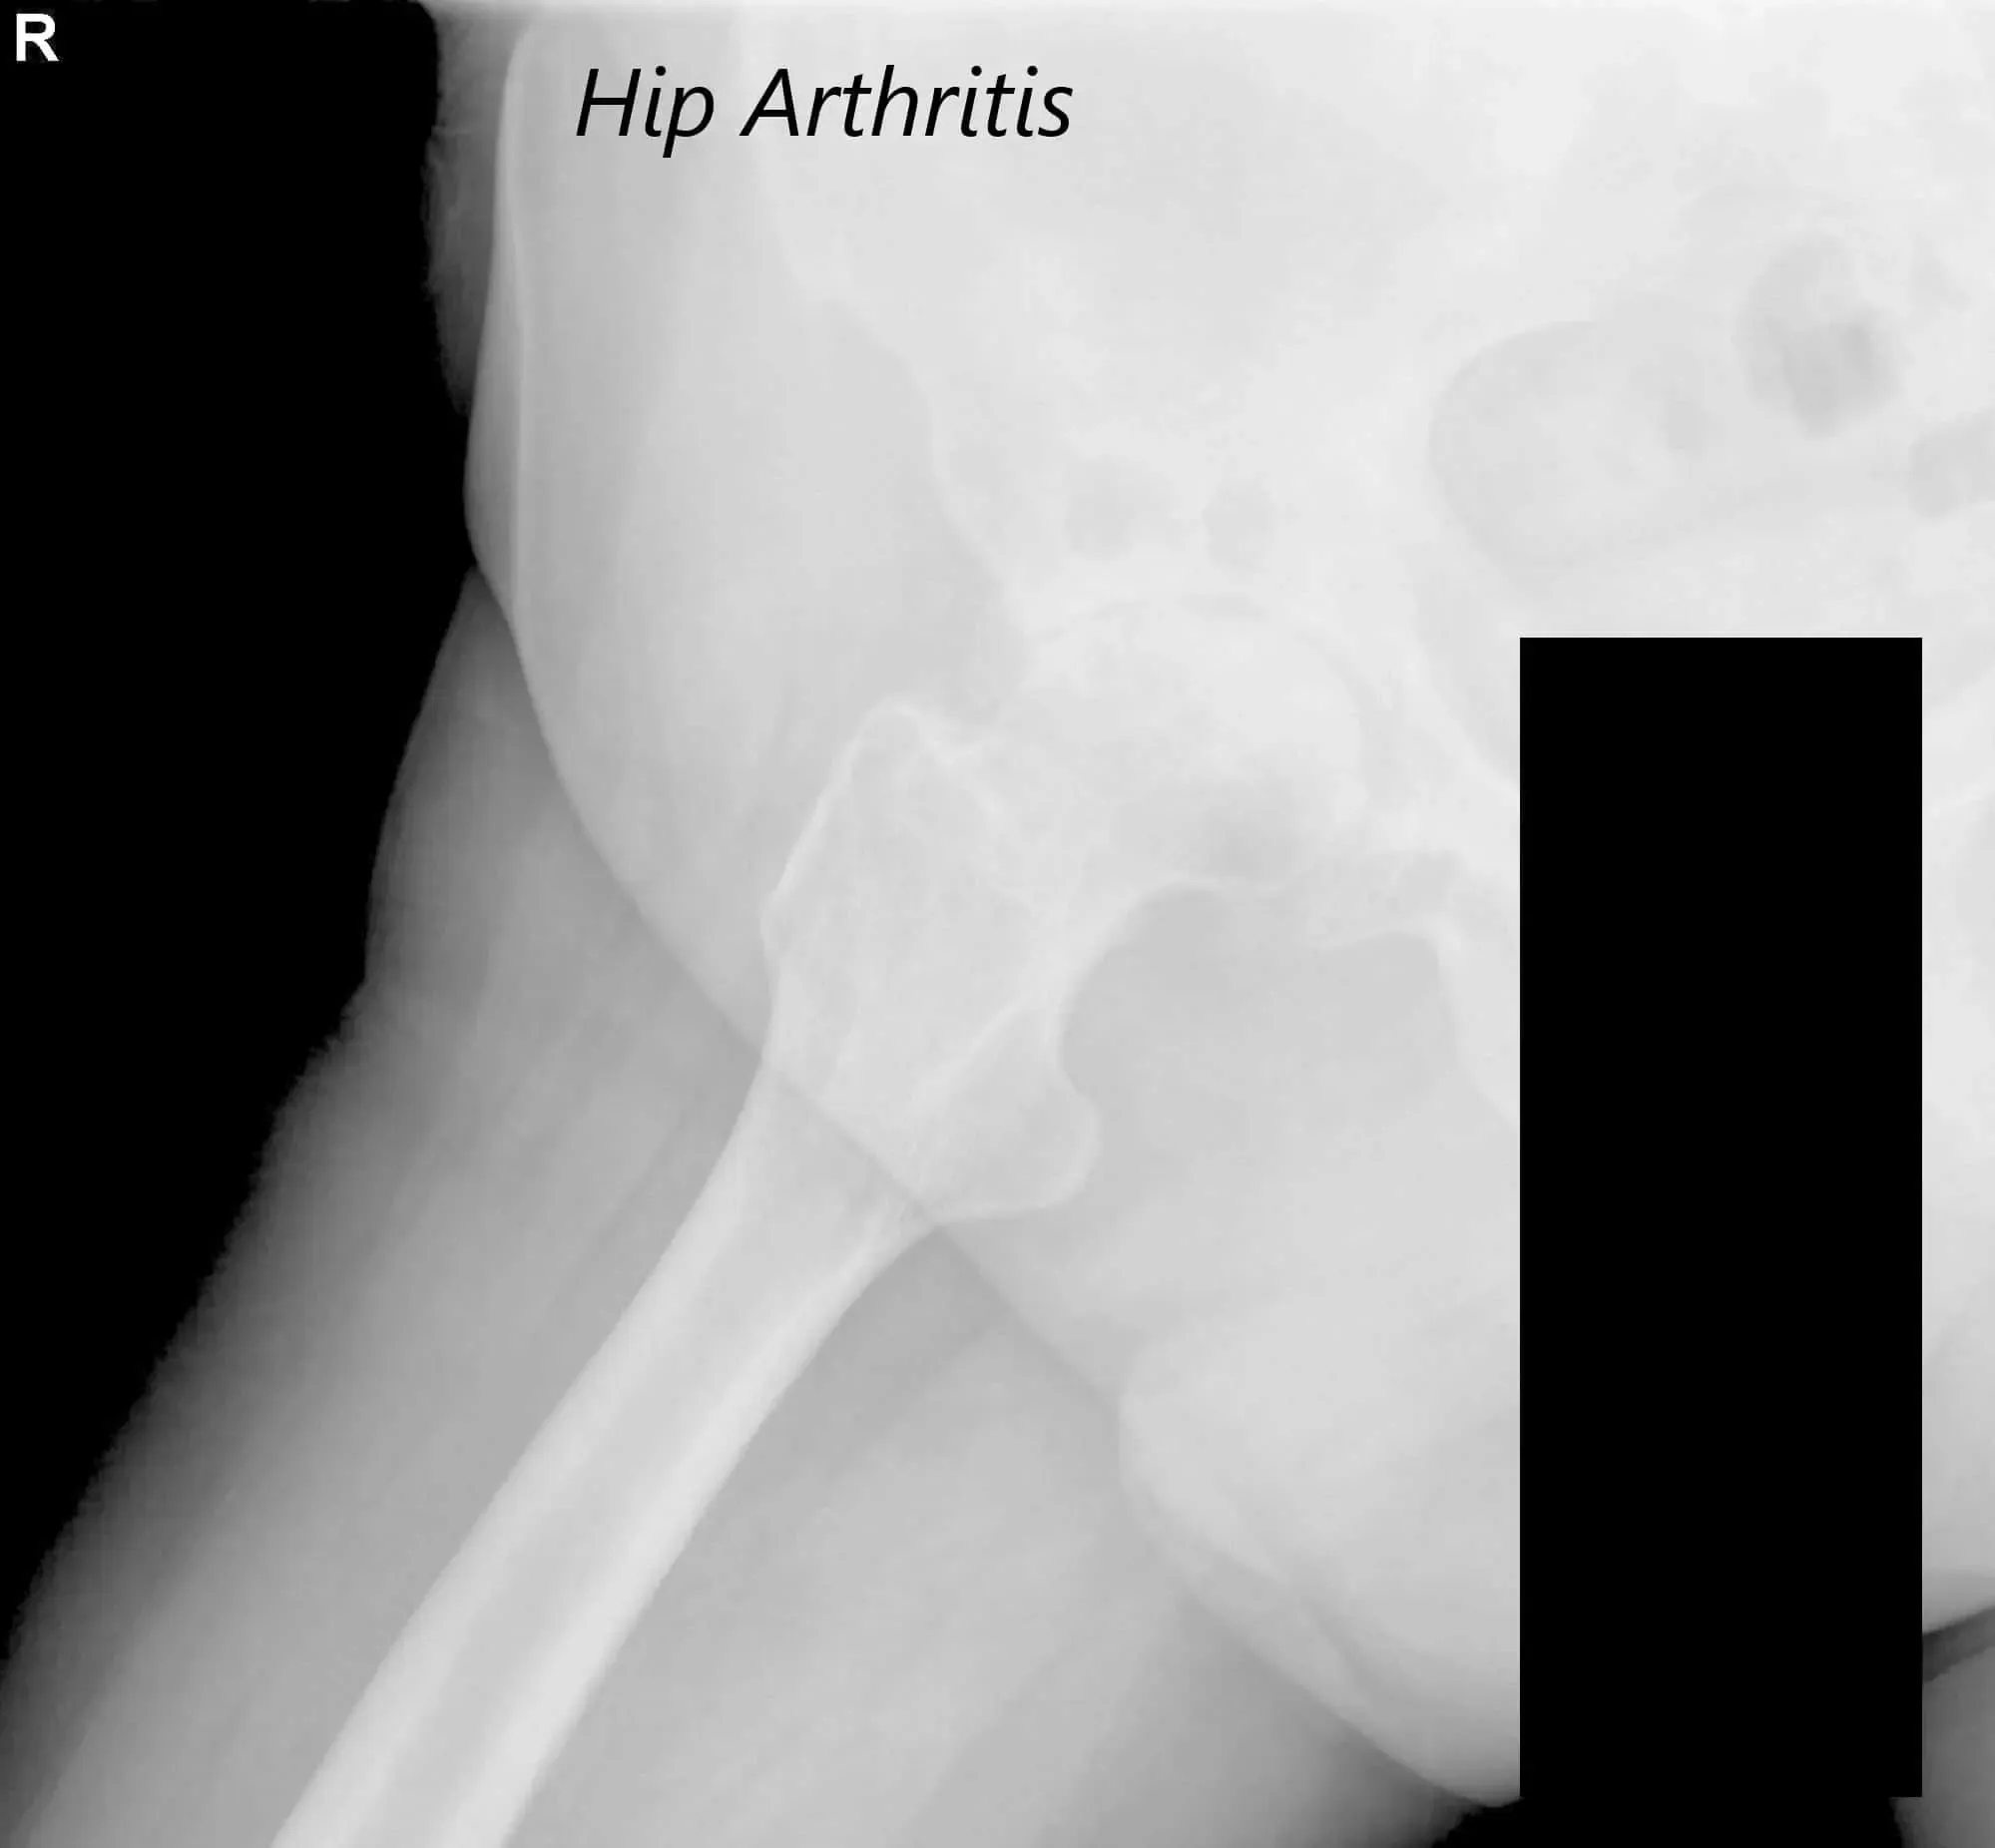

There was bilateral anterior Hip joint line tenderness. The bilateral digital Bryant triangle was comparable suggesting no suprapelvic shortening or lengthening. Imaging studies revealed severe bilateral hip arthritis.

AP view of the Pelvis X ray showing both hip joints with frog leg lateral views of the right and left hip joints suggesting severe bilateral osteoarthritis of the hip joints.